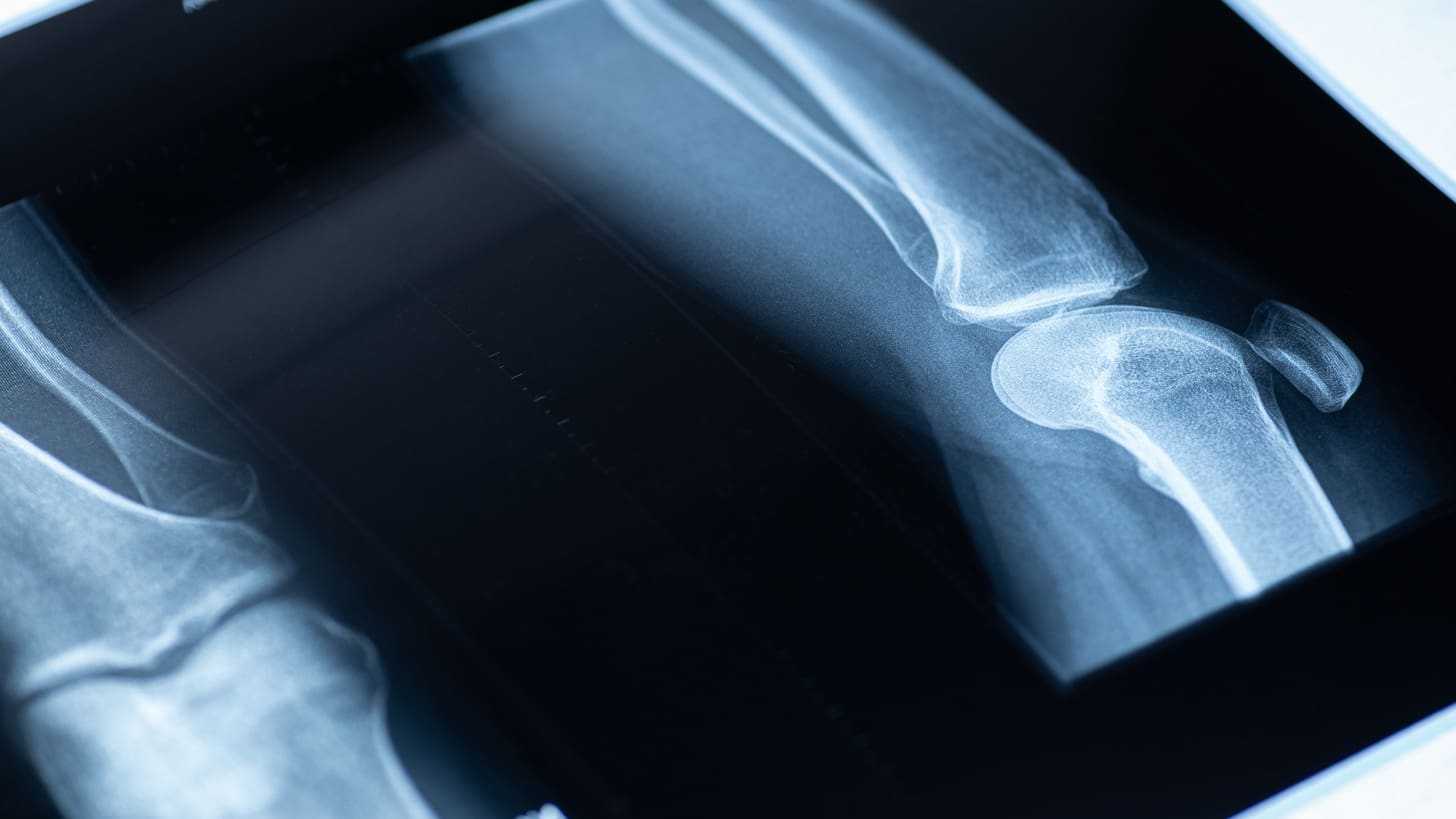

Imaging Methods: X-rays, MRI, and Ultrasound

We use different imaging methods to confirm the diagnosis. X-rays show bone issues, while MRI and ultrasound give us clear pictures of soft tissues. This helps us see how far the disorder has spread.